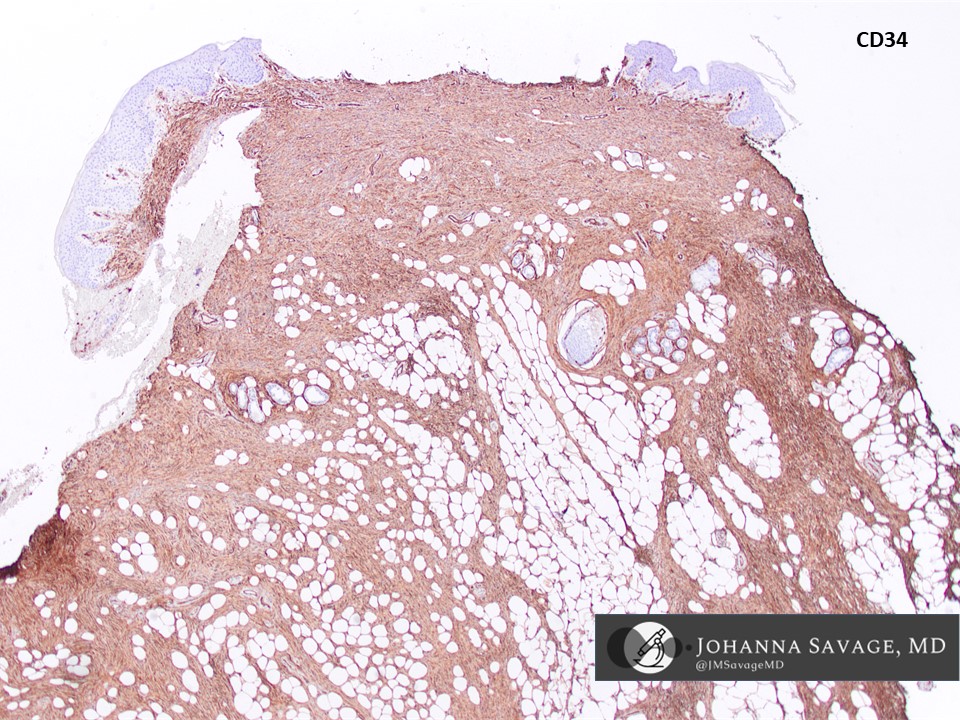

DFSP of the vulva - an uncommon location. These are low-to-intermediate grade sarcomas that are locally aggressive and often recur. Mainstay of treatment is surgery. Metastasis is rare. CD34+, S100-, Desmin-, SMA-, CK-, STAT6- #vulva #pathtwitter #gynpath #dermpath #BSTPath

DFSP of the vulva - an uncommon location. These are low-to-intermediate grade sarcomas that are locally aggressive and often recur.  Mainstay of treatment is surgery. Metastasis is rare.  CD34+, S100-, Desmin-, SMA-, CK-, STAT6-